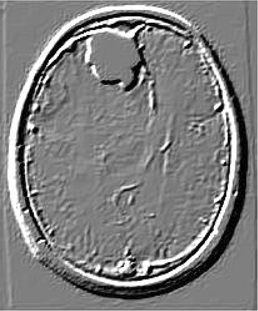

Table 6 Fused image output.

From: Multimodal medical image fusion combining saliency perception and generative adversarial network